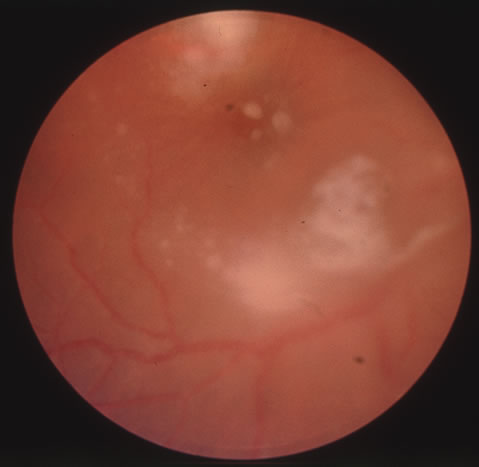

Diagnosis of varicella is usually not difficult, given the frequently obtainable history of exposure to a preexisting case and the characteristic rash. Serologic confirmation can be obtained by demonstrating increasing anti-VZV antibody titers. Multinucleated giant cells and eosinophilic intranuclear inclusions can be demonstrated by Papanicolaou's or other stains of smears from acute skin lesions. The clinical diagnosis of herpes zoster can be made in the presence of the characteristic vesicular lesions in a dermatomal distribution. Scrapings of the lesions demonstrate giant cells and intracellular inclusions. It is important to note that although most patients with herpes zoster are otherwise healthy, the possibility of an underlying systemic illness should be considered if the patient is young (i.e., younger than 50 years old) or the history suggests other systemic problems. The treatment of varicella is primarily supportive, consisting of analgesia, antipyretics, antipruritics, and good skin hygiene to prevent secondary infection. The use of aspirin in children is to be avoided in view of the belief that it may predispose to Reye's syndrome following varicella. Most eye disease is mild and self-limited and does not require treatment. Oral acyclovir (Zovirax) given five times daily early in the course of zoster infection has been shown to reduce the duration of viral shedding and the severity of acute pain. The greatest benefit is seen when medication is begun within 72 hours of onset of skin lesions. Two newer antiviral agents available for the treatment of herpes zoster are valacyclovir (Valtrex) and famcyclovir (Famvir). These agents have the advantage of a simpler dosing regimen, three times daily rather than five times daily with acyclovir, and a more favorable pharmacokinetic profile.13 It is thought that famcyclovir may also help speed resolution of postherpetic neuralgia. Valacyclvoir and famcyclovir are now preferred to acyclovir as first-line therapy for the treatment of zoster. They are well-tolerated drugs with few systemic side effects other than a requirement for reduced dosing in patients with renal failure. Oral corticosteroids also seem to have a beneficial effect in reducing acute pain and speeding cutaneous healing. They have not been shown to have an effect on postherpetic neuralgia. Topical corticosteroids and cycloplegics are commonly used to treat the inflammation associated with herpes zoster ophthalmicus.10 Tear supplements, bandage contact lenses, surgical correction of lid abnormalities, and tarsorrhaphy may be necessary to promote the healing of epithelial defects. Vision-threatening pathologic processes such as chorioretinitis and optic neuritis should be treated aggressively with intravenous acyclovir and high doses of prednisone. Treatment of postherpetic neuralgia is often disappointing. Routine analgesic drugs are generally ineffective. Cimetidine, colchicine, phenothiazines, and tricyclic antidepressants have been used with some success. Capsaicin cream and lidocaine patches may also be applied for local relief. The pain tends to slowly diminish and disappear over the course of 1 to 2 years but may be prolonged, especially in elderly patients. For those with severe intractable pain, intrathecal injection of methylprednisolone acetate once weekly for 4 weeks has recently been shown to provide relief.14 CYTOMEGALOVIRUS INFECTION Cytomegalovirus (CMV) is a herpes virus responsible for severe congenital malformations, a mononucleosis syndrome in young adults, and disseminated lesions in the immunosuppressed, especially retinal infection and pneumonia in patients with acquired immunodeficiency syndrome (AIDS). Patients with AIDS with CD4 counts between 50 to 100 cells per microliter are particularly susceptible to CMV retinitis. If the retinitis is untreated the prognosis is very poor often resulting in full-thickness retinal necrosis and blindness. Despite treatment, CMV retinitis often recurs in up to 50% of cases.15 In the United States, 20% of people are seropositive for CMV by age 20. Approximately 1% of infections are congenital and 5% perinatal. Anti-CMV immunoglobulin (Ig) G is present in greater frequency in homosexual men, on the order of 80% to 90%. The virus may be transmitted via blood, cervical secretions, semen, and breast milk and as an intrauterine infection. Serologic testing for CMV is not routinely performed because of this frequent exposure in the general population. Approximately 10% of congenitally infected newborns have permanent sequelae. The full syndrome is manifest as hepatosplenomegaly with hepatitis and cirrhosis, maculopapular rash, purpura, hemolytic anemia, pneumonia, microcephaly, microgyria, encephalitis, chorioretinitis, pathologic bone fractures, and growth retardation. Otherwise asymptomatic children may develop late sensorineural hearing loss or mental retardation. In normal older children and adults, the most common manifestation is an atypical mononucleosis, comprising fever and lymphocytosis with atypical lymphocytes. Lymphadenopathy and pharyngitis may be present, and rubelliform rashes occur. Heterophil antibodies are negative. In the immunocompromised, especially organ transplant recipients and patients with AIDS, CMV commonly is responsible for serious clinical syndromes. It causes an interstitial pneumonia, resulting in dyspnea and dry cough, with interstitial infiltrates on the roentgenogram. Subacute encephalitis, enterocolitis, adrenalitis, and adrenal necrosis may be noted. CMV retinitis is common in patients with AIDS. Perivascular granular white or yellowish infiltrates with hemorrhage are typical (Fig. 7). Minimal vitritis or anterior uveitis may be present. The posterior pole, including optic nerve, or peripheral retina may be involved. Optic neuritis may be retrobulbar. Resolution of retinal lesions reveals local retinal atrophy and pigment dispersion. Iridocyclitis may occur secondary to infection of ciliary processes. CMV retinitis in patients with AIDS is considered a poor prognostic sign in terms of life expectancy. Congenital CMV infection may also cause retinitis, as well as anterior uveitis, cataract, and optic atrophy. New foci of retinochoroiditis can develop in later years of congenital infection, and such infants require periodic reexamination as long as virus is shed in the urine.